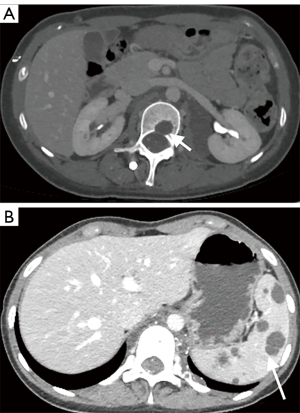

The involvement locations and incidence of bone lesions in 39 cases are detailed in Table 2. According to the morphology of bone lesions, these were divided into the following four types: (I) cystic changes (n=30; Figure 2), which showed single or multiple round-like cystic hypodense shadows in bone. The lesions had clear borders with or without sclerotic margins, and the maximum diameter was less than 5 cm. Marginal sclerotic margins (n=28), with one case showing iodized oil deposits within the lesion. (II) canal-like or honeycomb-like changes (n=34; Figure 3), which showed a tortuous, tubular distribution of hypointense shadow with clear margins and continuous at multiple levels above and below. The bone cortex was smooth or irregularly fractured in a worm-like pattern, while lesions were seen in 20 cases with iodized oil deposits. (III) Osteoporosis-like changes (n=16 cases; Figure 4), which showed a diffuse decrease in bone density and thinning of bone trabeculae. No lipiodol deposition was seen in any of the 16 cases in this group. (IV) Osteosclerosis-like changes (n=8; Figure 5), with two cases showing smooth thickening of the bone cortex, three cases showing increased density of osteophytes in the medullary cavity, three cases showing mixed presence, and five cases showing narrowing of the medullary cavity. Iodized oil deposition was not observed in any case.